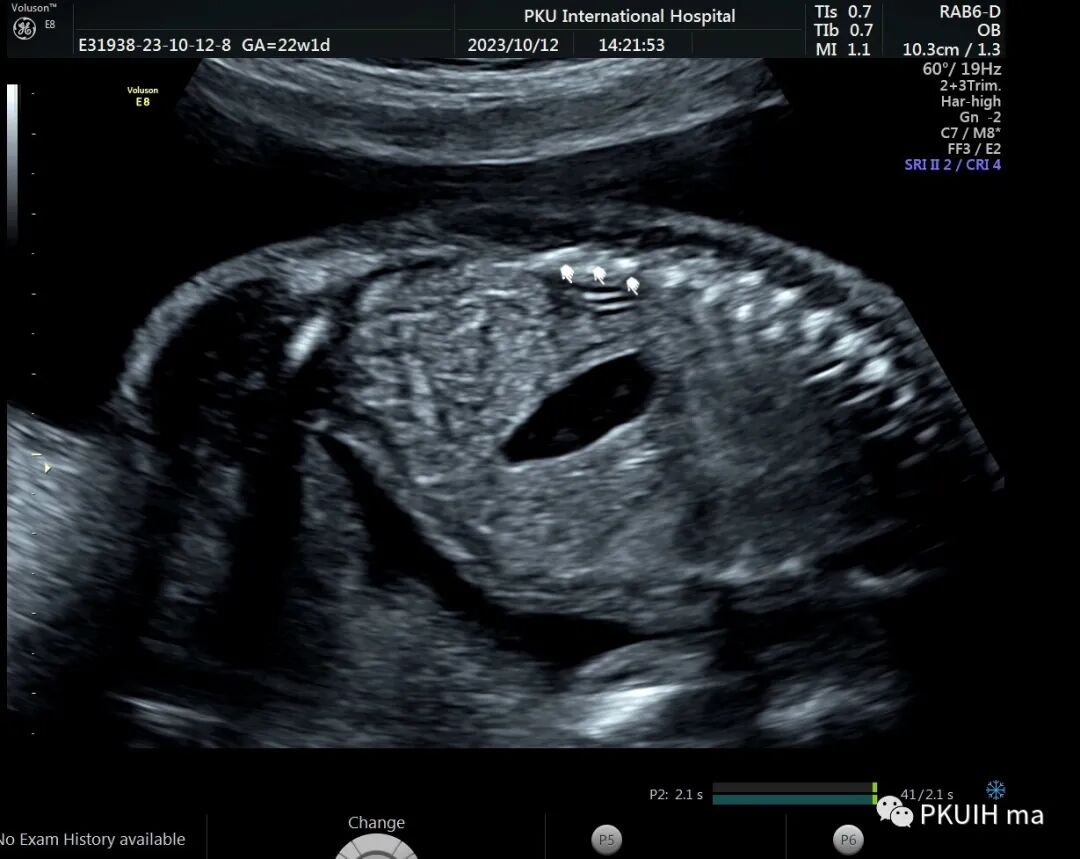

右肾大小位置正常,右肾动脉可见,左肾动脉缺如,正常的左肾区未见肾组织回声,可见肾上腺平卧。于膀胱后上方见一肾组织回声,大小约1.5x1.4x1.0cm,皮髓质分界欠清晰,血供来源于髂动脉。

异位肾较常见,发生率约1/1200,目前产前确诊并不困难。异位肾最常见的就是盆腔异位肾,占异位肾的一半以上,往往合并发育不良。血供可来源于腹主动脉或髂动脉,部分可有血管迷走。超声诊断标准:1、一侧肾区内未见肾组织回声;2、同侧的肾上腺呈平卧征;3、对侧肾可增大也可正常;4、盆腔可见一发育不良或发育正常的肾脏回声;5、可合并其他畸形,比如输卵管发育畸形或者是Vacterl综合征。